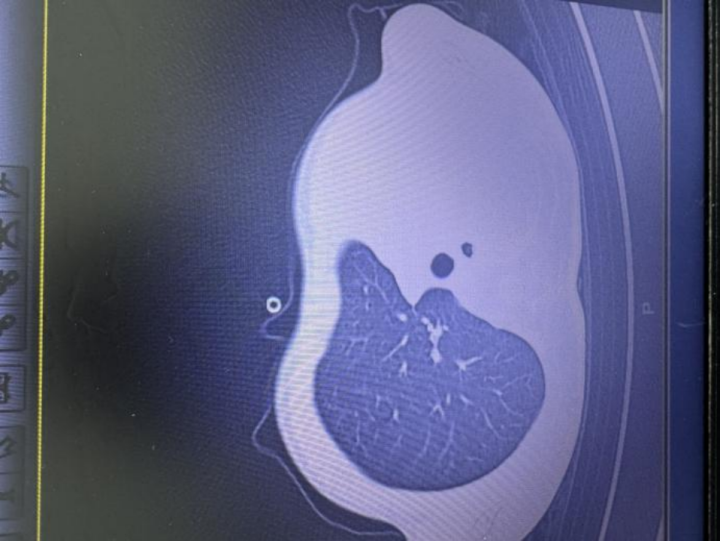

急診檢查結(jié)果讓醫(yī)護人員瞬間緊張:驗血顯示炎癥指標大幅上升,胸片更發(fā)現(xiàn)左側(cè)肺葉幾乎“不工作了,影像學中變成大片白色,即通常所說的“白肺”,意味著肺功能嚴重受損,孩子已經(jīng)缺氧,隨時有窒息危險。

圖:影像顯示肺白了一半